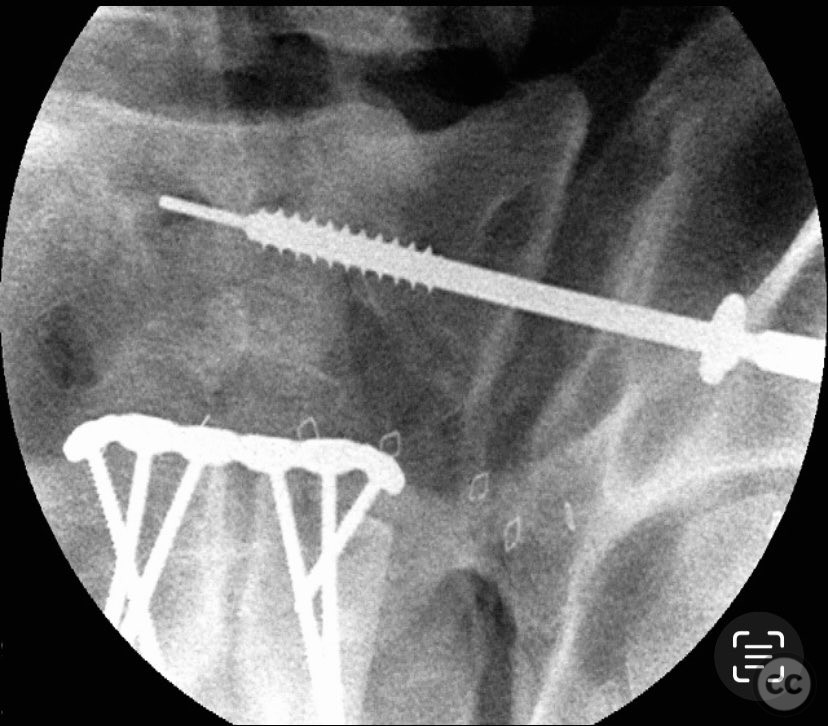

Anatomical surgical approach:  A lower midline infraumbilical incision was made to expose the symphysis pubis. Subperiosteal dissection was performed to mobilize the rectus abdominis insertions and expose the pubic bodies. A pelvic reduction clamp was applied with tines docked in dense bone or soft tissue as dictated by local tissue quality, oriented to correct deformity while avoiding interference with planned plate placement. Following reduction, a contoured anterior symphyseal plate was applied and secured with cortical screws. Upon removal of the clamp, persistent SI joint malreduction was noted. Under fluoroscopic guidance, a percutaneous pathway was prepared for a cannulated iliosacral lag screw, traversing the posterior ilium into the upper sacral segment, ensuring safe passage relative to neurovascular structures.

The intraoperative course revealed that indirect reduction of the incomplete SI joint injury via anterior stabilization was insufficient, necessitating direct percutaneous fixation. A single cannulated iliosacral oblique lag screw was inserted under fluoroscopic control, achieving reduction, compression, and stabilization of the SI joint. Surgeon-specific technical consideration included avoidance of large-diameter drills for the posterior ilium due to limited bone stock (approximately 3 cm of ilium available for purchase), and the preference for an appropriately sized washer to optimize compression without risking iatrogenic fracture.

Orthopaedic implants used:   3.5 mm anterior symphyseal plate with cortical screws; 7.0 mm cannulated iliosacral lag screw with washer